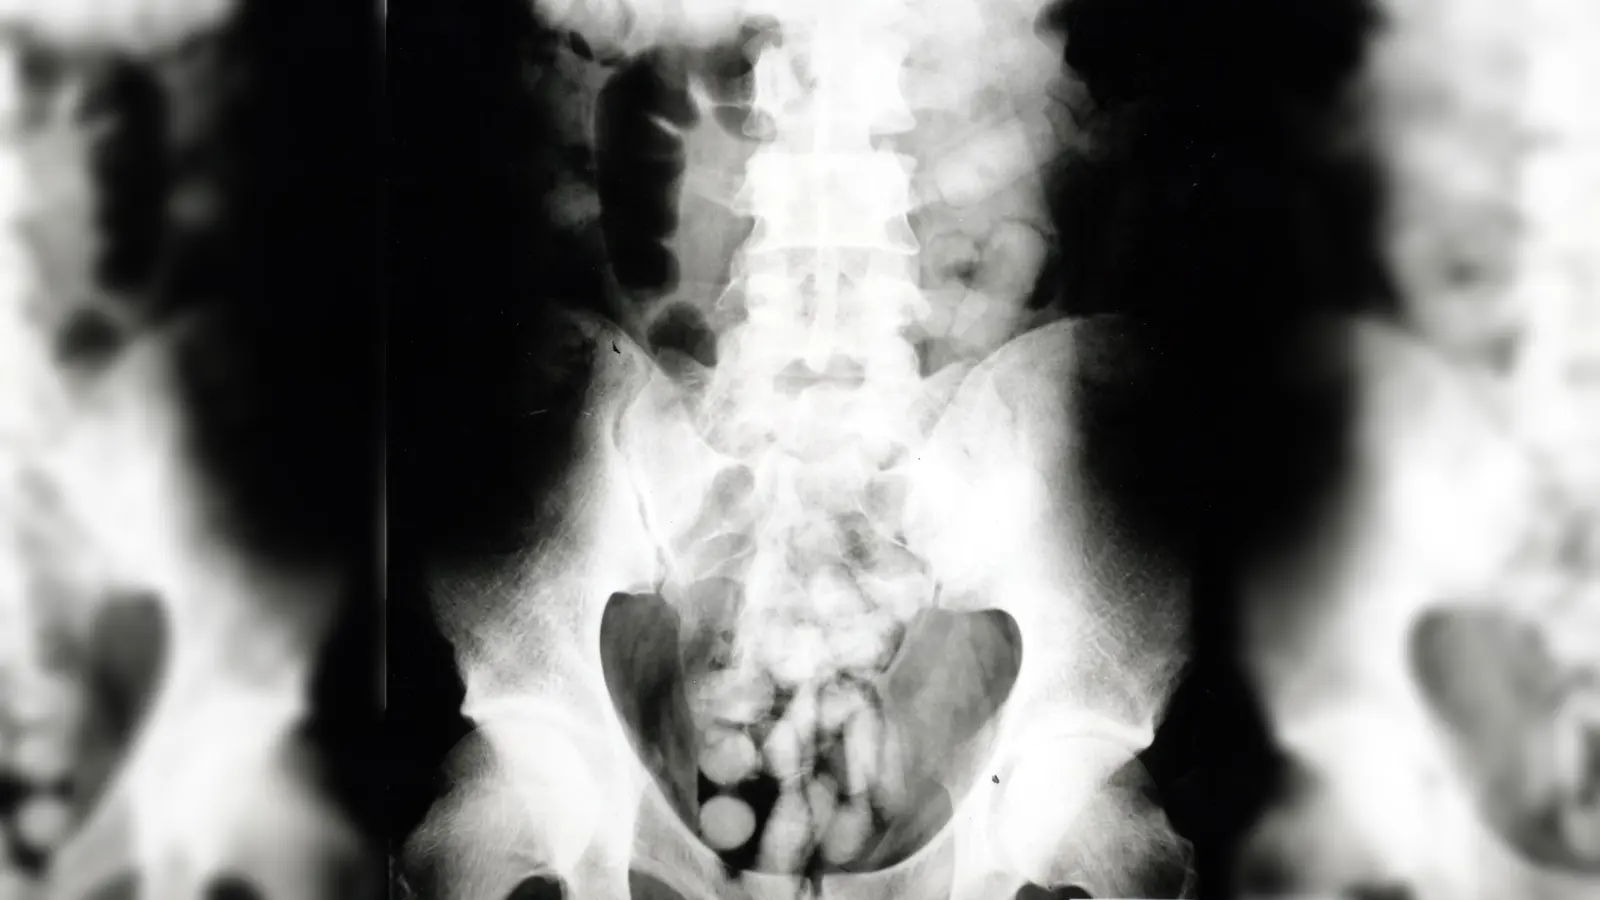

Bei der Zollkontrolle verstrickte sich kürzlich ein Mann, der aus Brasilien nach Großbritannien reisen wollte, am Flughafen in Widersprüche. Ein angeordneter Drogenwischtest zeigte Kokain. Da sich beim Kolumbianer kein Kokain fand, musste er im Krankenhaus geröntgt werden. 90 Schluckbehältnisse („Bodypacks”) kamen bei dem 36-Jährigen zum Vorschein. „Das Röntgenbild zeigte Fremdkörper und bestätigte den Verdacht”, so Pressesprecherin Marie Müller. Das Verschlucken von Drogen zum Transport wird als Bodypacking bezeichnet. Drogen werden dazu in speichel- und magensäureresistente Beutel verpackt. Platzt nur einer, bedeutet das meist den Tod. Es wurde Haftbefehl erlassen, weitere Ermittlungen laufen.